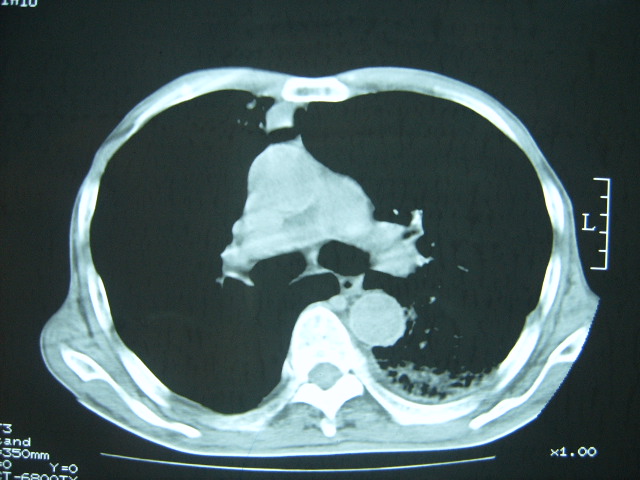

男74岁,咳嗽,寒战,低烧。有糖尿病史。

两肺结核,空洞形成,左下肺肺段隔离症待排

考虑:1、左下肺脓肿;

2、双肺结核。

考虑:糖尿病合并:1、左下肺炎继发肺脓肿;

考虑:1、左下肺脓肿;不排除霉菌感染

1、左下肺肺脓肿,合并霉菌球形成?.2、双肺陈旧性病灶.3、右上肺病灶警惕瘢痕癌,建议定期复查.

两肺结核,左下肺大片实变,内见空洞性病变,壁不规则,结合糖尿病史,考虑:结核性?霉菌性?建议结合实验室检查或治疗后复查。